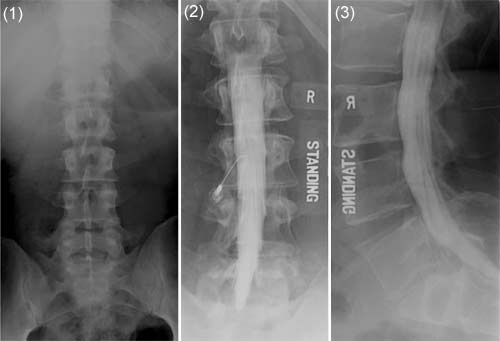

Lumbar Spine X Ray Ap Left Image And Lateral Right Image Views Download Scientific Diagram

Assesment Of The X Ray Features Of Lumbar Disc Degeneration Lateral Download Scientific Diagram